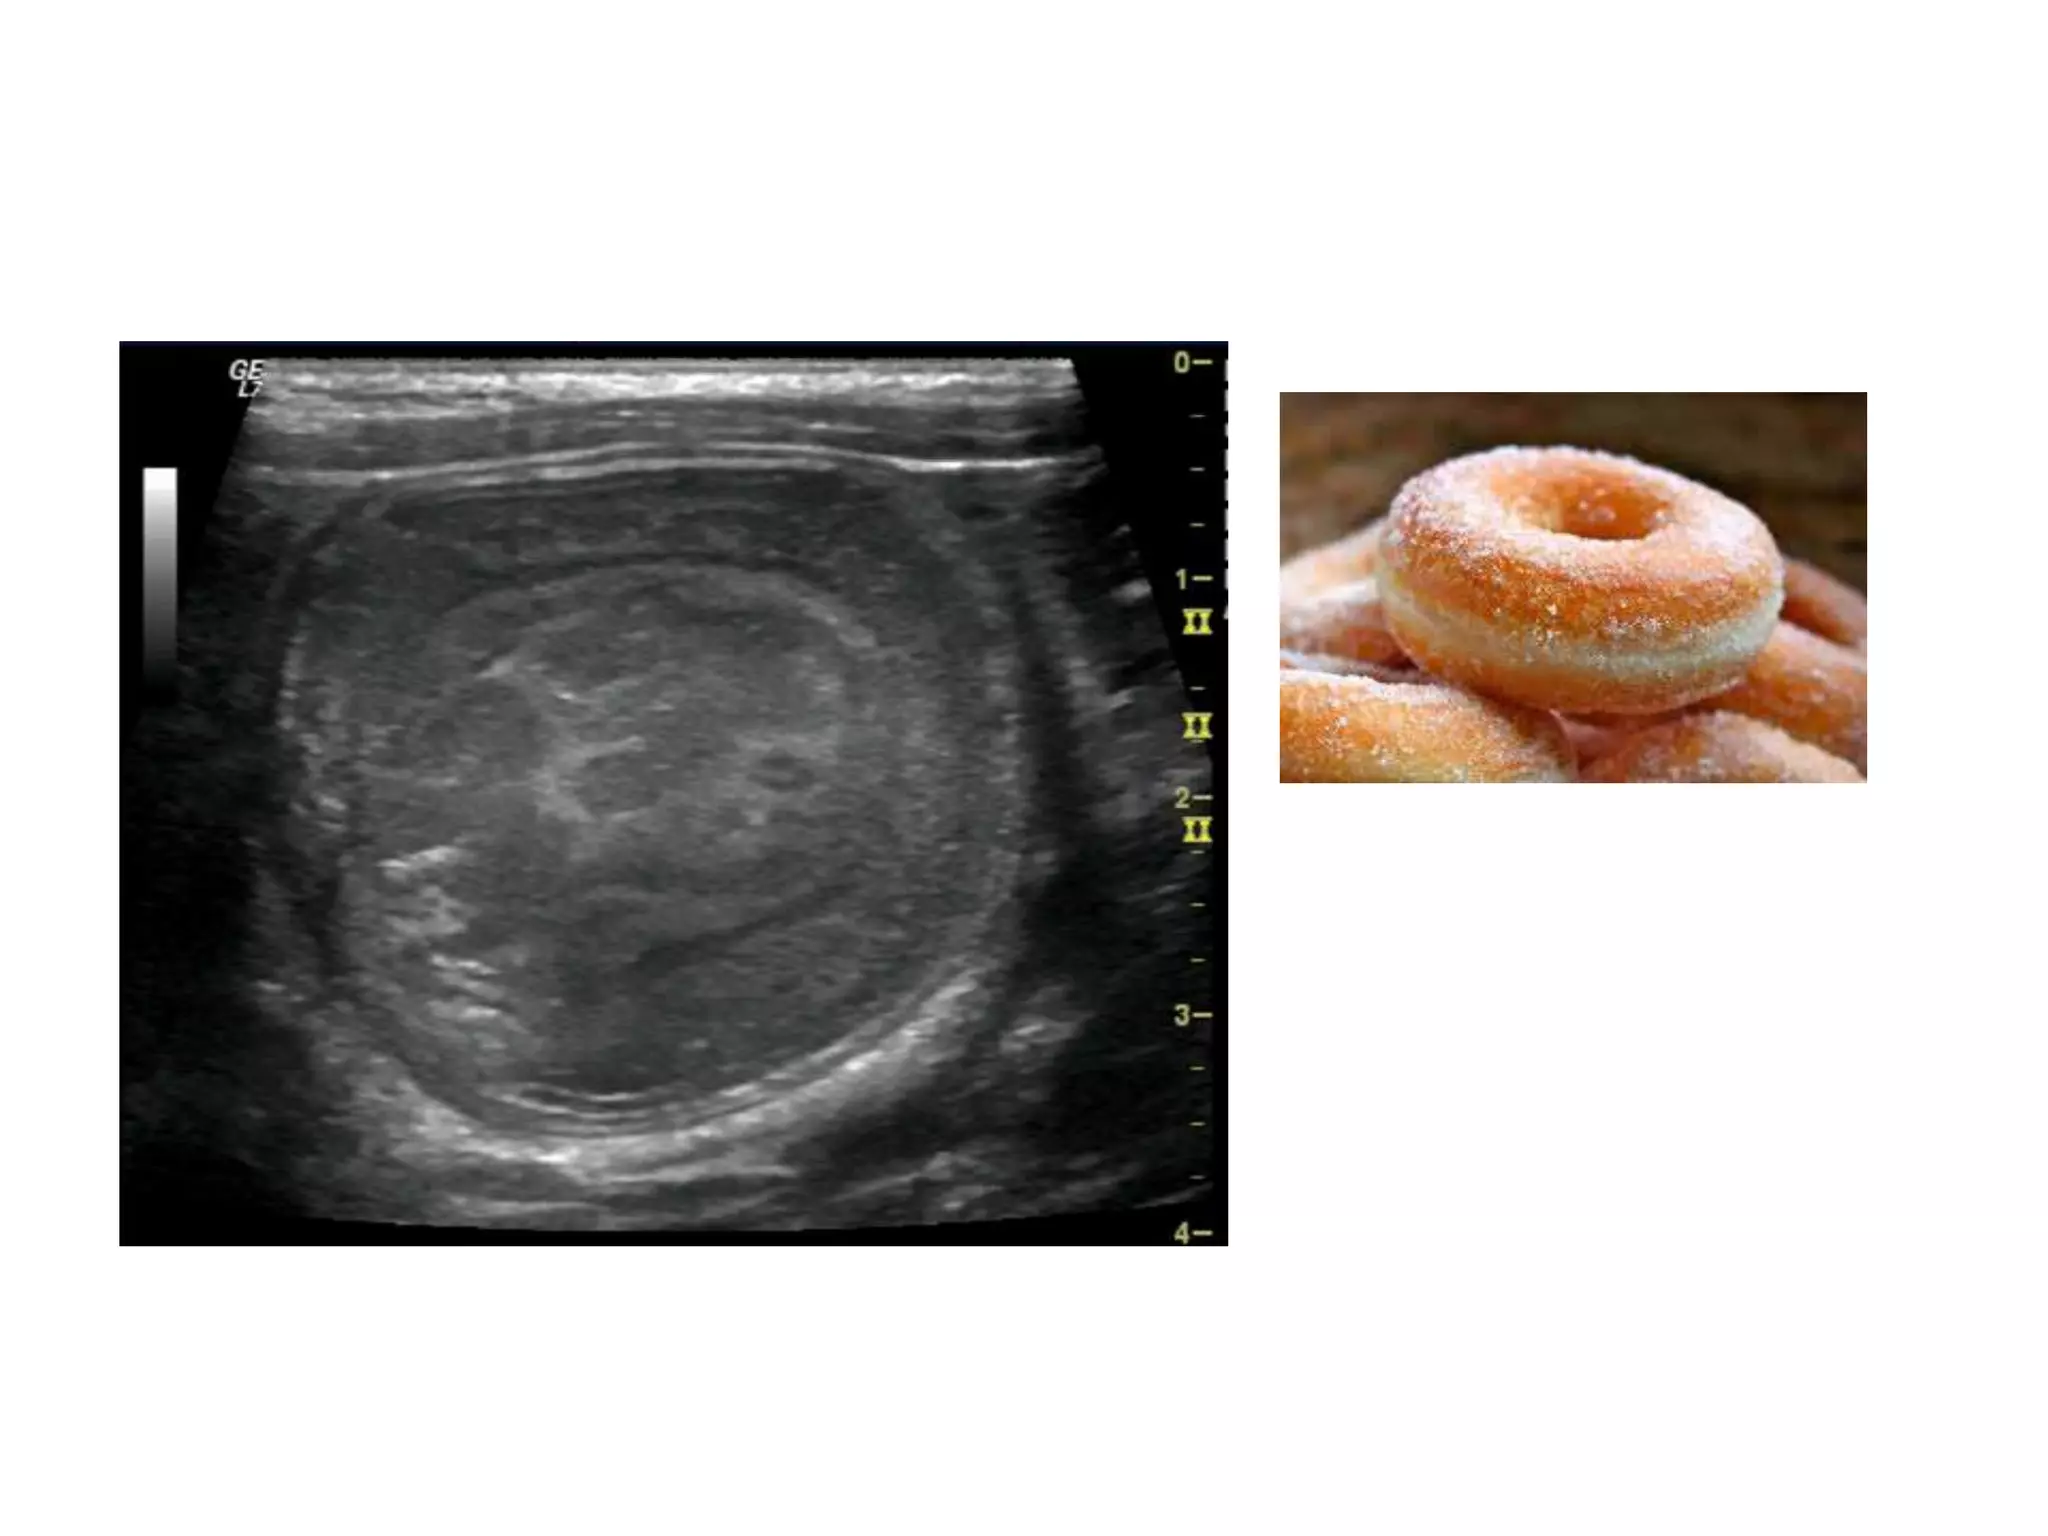

This document provides an overview of infantile hypertrophic pyloric stenosis (IHPS). IHPS is a condition characterized by hypertrophy of the pyloric muscle which causes failure of the pylorus to relax. It typically presents in infants between 2-5 weeks of age with projectile vomiting after feeding. On examination, an olive-sized mass may be palpated in the epigastric region. Diagnosis is confirmed through imaging studies showing dilation of the stomach and "string sign" on barium studies. Treatment is through pyloromyotomy to divide the thickened pyloric muscle.